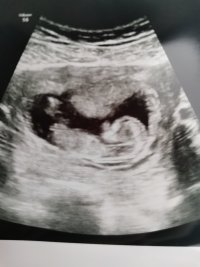

13+3 i dag, veldig livlig og lite samarbeidsvillig

. Skulle bare ligge og glane inn i ryggen min, men ellers veldig aktiv da. Jordmor holdt på leeenge for å prøve å snu den, men den spratt bare tilbake med en gang hver gang. Hun satt på noe som skaper litt varme fordi de kan reagere på det og bevege seg, jeg gikk litt rundt, prøvde å hoste hardt ned magen, hun prøvde å skikkelig kna på magen.. Men nei!

Hun målte alt mulig av lengder, organer og hulrom og alt ser riktig ut. Hurra!

Gadd ikke engang å spørre om sjans for å se nub, var viktigere å få sett nesebeinet og de andre tingene. Lårbeinet er nå 0,95 cm. Rart å tenke på!